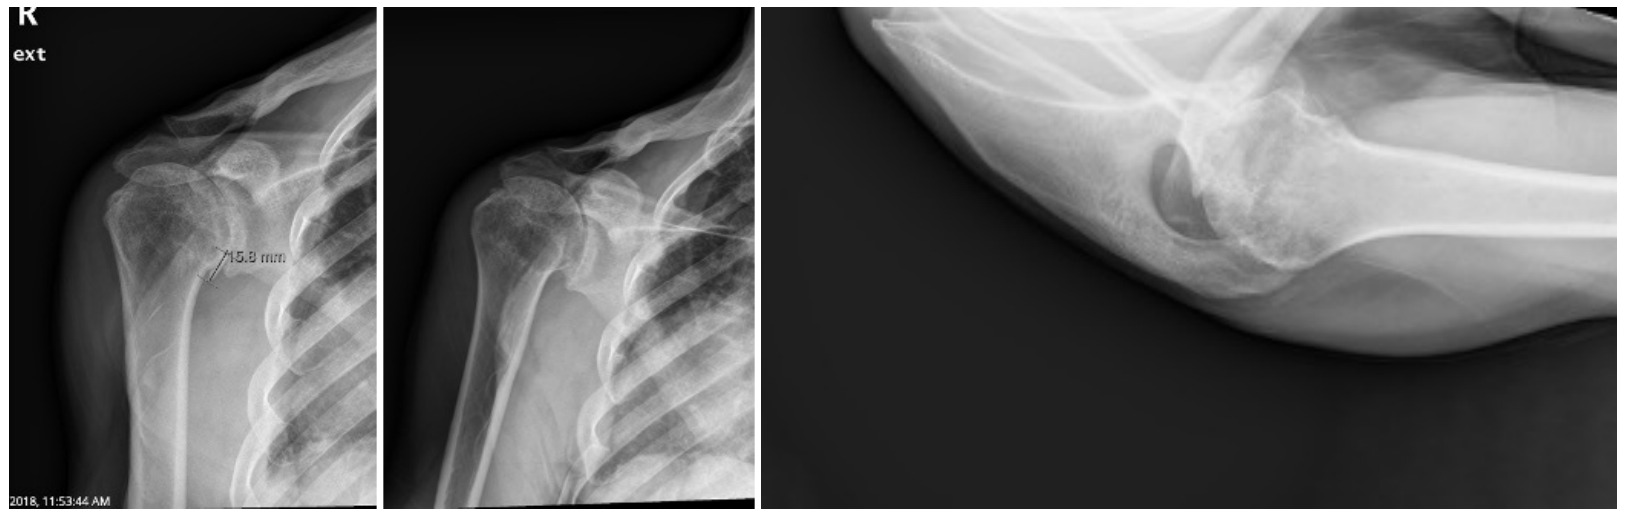

Case one is a 58-year-old male who is an avid golfer with long standing right shoulder pain. Surgical history includes previous Bristow procedure 30 years prior. Current Subjective Shoulder Value (SSV) is 30% and pain is 8/10 at baseline. Active range of motion was 110° of forward flexion, -10° of external rotation and interna rotation to the lateral buttock. Radiographs (Figure 1) and computed topography (CT) scan (Figure 2) show retained implants with loss of joint space, glenoid retroversion, and significant posterior humeral head subluxation. The patient had failed conservative management and was indicated for arthroplasty. Due to significant posterior bone loss and retroversion, an augmented anatomic component was selected for this patient. Radiographs at one year show a well seated glenoid component with restoration of the joint line and a centered humeral head (Figure 3). At five years, SSV had improved to 95% with excellent clinical motion (Figure 4).